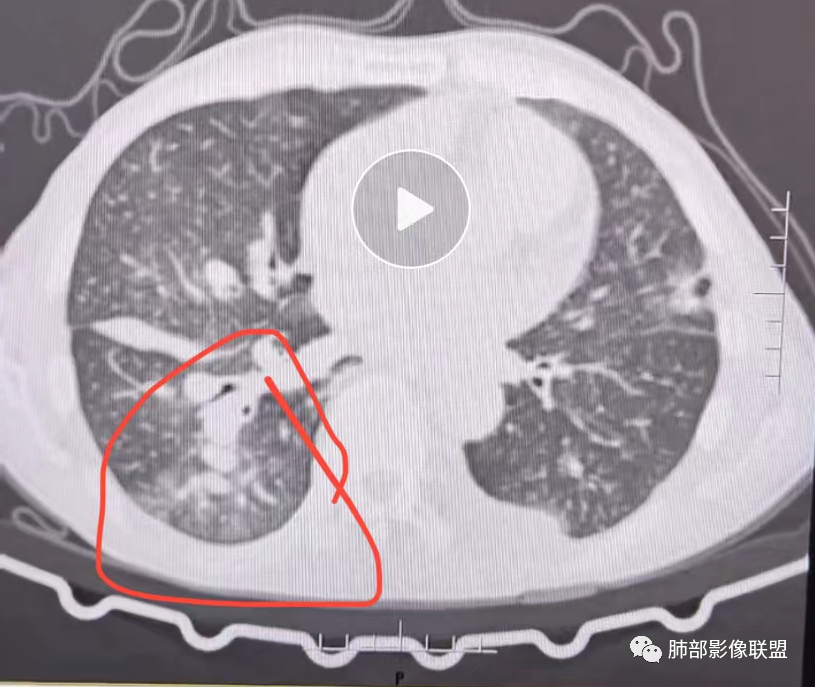

老年男性,胸闷、浮肿10天,左肺尖可见肺大泡影,两肺散在纤维索条影,右肺见弥漫性腺泡结节,以右肺上叶为著,右肺下叶局部小叶间隔增厚,双侧胸腔、右侧叶间裂及心包积液,结合实验室及影像检查,符合心衰及肺水肿表现,右肺部病变符合PVOD表现。

双肺透过度不均匀,右肺减低,可见腺泡结节影,中央间质、周围间质增厚,少量积液。肾衰病史首先考虑肾性肺水肿。

肺水肿有的,可能心源性的,但导致的原因仍需进一步排查,虽有肾功能但不像肾源性,虽有肺动脉高压,但不考虑PVOD(年龄,性别,肺动脉高压可能由于瓣膜,心衰继发)。二聚体高,右肺胸膜下反晕病灶,肺梗要排除。另外就是右单肺腺泡结节以及带晕的实性结节。这个怎么解释。虽有误吸危险因素,但临床没有发热,血象不高。

这些区域肺动脉增粗明显,围绕肺动脉周围GGO,但是局部小叶间隔不增厚,按理应该考虑肺动脉高压所致肺部改变

这些小叶间隔增厚明显区域反而GGO少

3、右肺改变符合肺动脉高压导致

2.右肺广泛密度增高、腺泡结节样磨玻璃影,血管影明显扩张,小叶间隔增厚。

3.右肺下叶纤维钙化灶。

4.左肺相对广泛低密度、血管纤细(显著)。